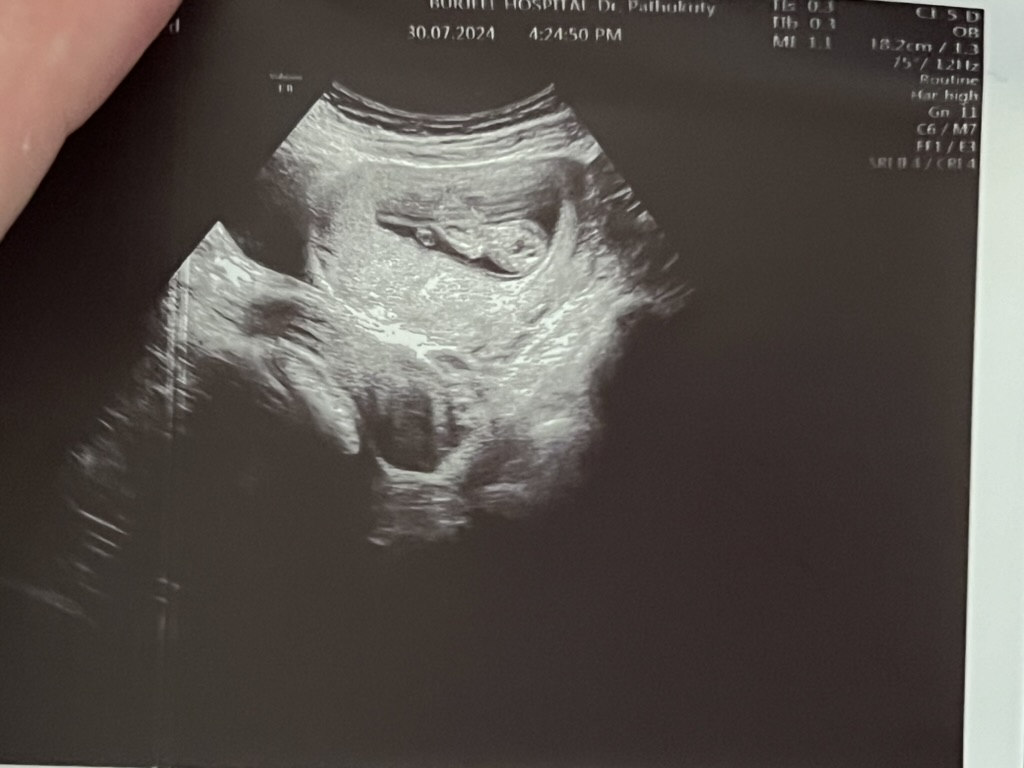

First thing we did when we got back was to try and figure out what was up. The first thing the doctor asked was "when was her last period". Blasphemy! There's no way Chinatsu was pregnant. She did stop with the pill, but only a few weeks ago, and my pull-out game is legendary.

"OK, I'll schedule a test anyway" the doctor said and we laughed. Then they pumped her full of a saline solution and send us off with some medicine. Chinatsu would continue to feel like shit for the next few weeks.

Aaaaand Chinatu is pregnant.

The baby continues to grow and continues to stay a baby! We learn it's a boy and we quickly decided to name him Thomas. Do not ask me what Neo's first name is. And do not insinuate a relation because it's definitely not related at all. Haha. (it is)